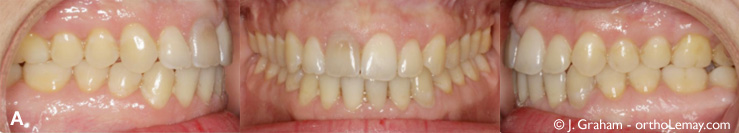

Fig (3) – Importante béance antérieure et constriction maxillaire (mâchoires étroites). Les flèches indiquent le mouvement d’ingression nécessaire sur les dents postérieures pour diminuer la béance antérieure. (D) Radiographie céphalométrique montrant la béance et le contact seulement entre les dents postérieures.